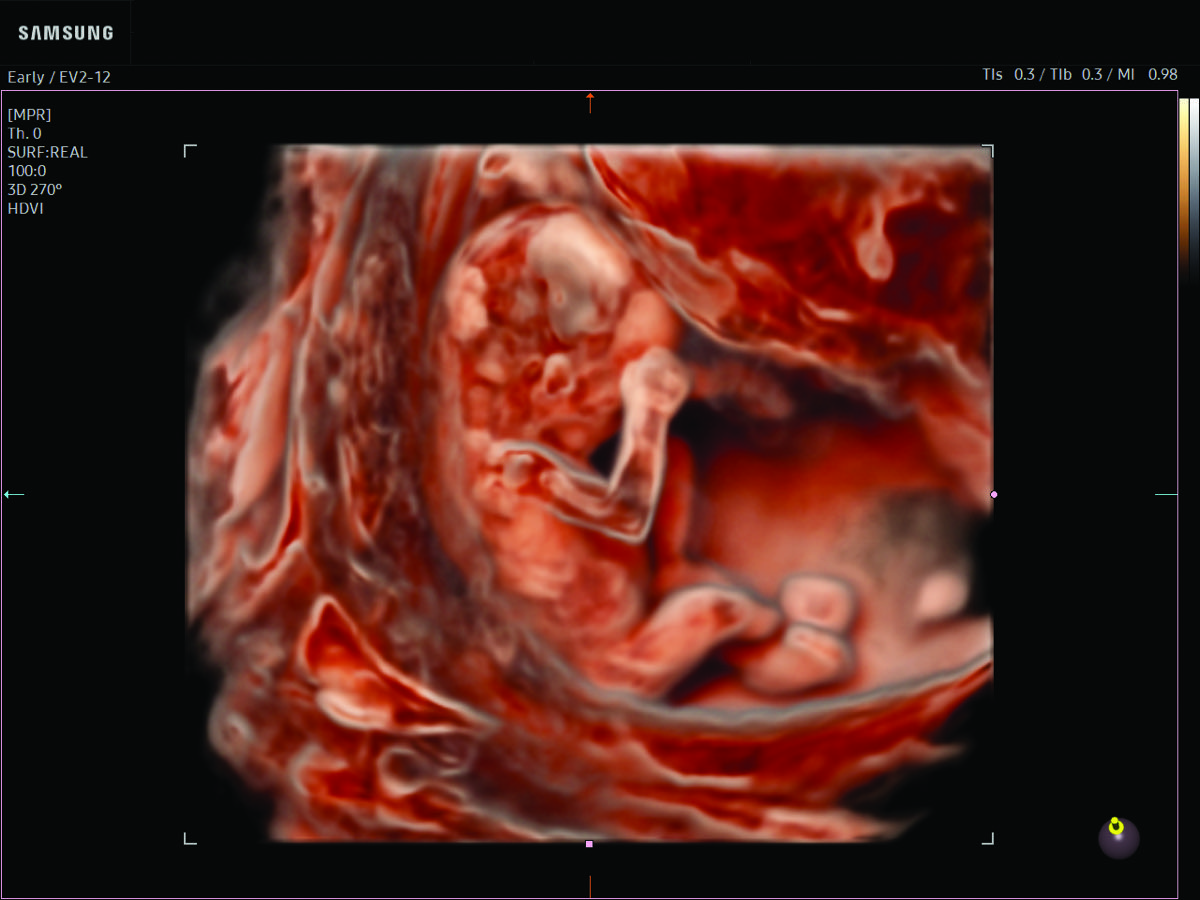

Comprehensive, advanced and expert MFM care for high-risk pregnancies

- Fetal anomalies